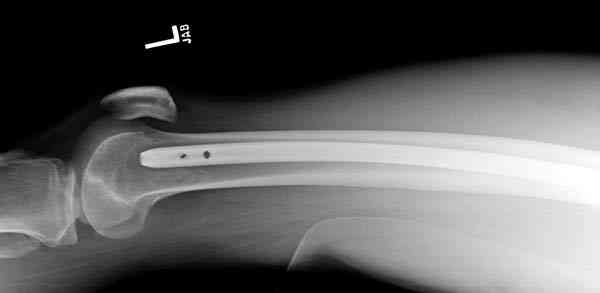

В нашем случае 21 летний боец уличного фронта, фиксацию провели на следующий день, зафиксирован интрамедуллярным штифтом. Не стали делать первичную хирургическую обработку точечной раны, зафиксирован как есть. Клинические снимки:

Конечно, наш случай не эталон, возможно, на месте вам виднее, может быть, нет необходимости ориентироваться на зарубежные ссылки, если получается лечить аппаратом Илизарова на месте, почему нет? Необходимо посмотреть собственный арсенал, чем фиксировать, и какая теория, иначе любой отличный метод можно превратить в источник остеомиелита.